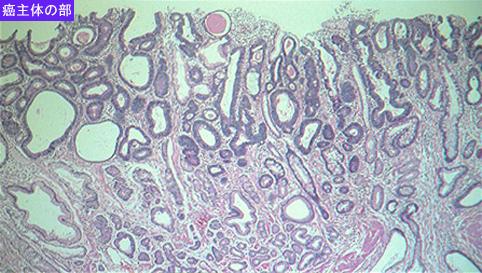

질환(병리주체)의 분류 악성 상피성종양/선암

부위(장기별) 위(부위)/위각

검사방법 마이크로

종양의 육안분류 0형(표재형)/IIa형(IIa+IIc)

종양의 최대경(밀리미터) 30~34

종양의 심달도 m